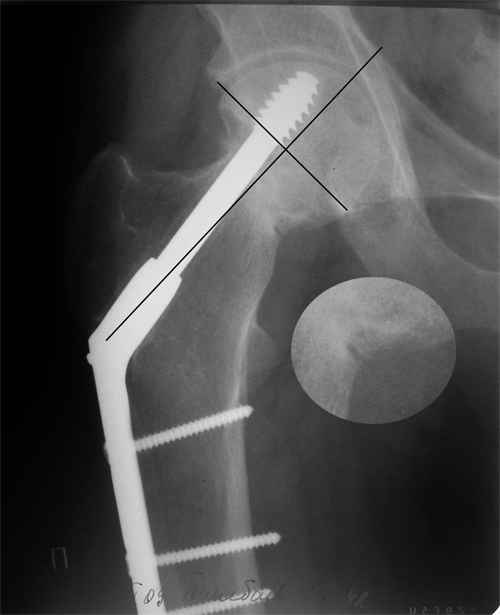

Больной Т. 1966 г.р.Травма 28.06.2007. Прооперирован в г. Бишкек, Оп:

Остеосинтез правого бедра системой DHS. В последующем беспокоили

периодические боли в правом тазобедренном суставе с иррадиацией в

коленный сустав в область передней поверхности правого бедра. Лечился

амбулаторно с незначительным эффектом.

В 07.04.2008 по 08.05.2008 года лечился в госпитале ГУВД и СО в

стационаре с Срастающийся перелом шейки правого бедра в условиях

фиксации системой DHS – боли уменьшились.Боли обострились 03.02.2009

внезапно, госпитализирован.

Результат - Псевдоартроз шейки правого бедра (имеются косвенные

признаки разрушения спонгиозной части головки бедра)Планируется -